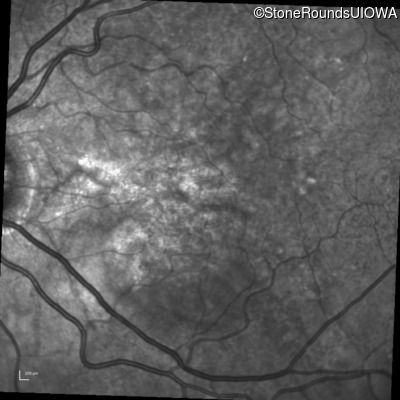

Infrared Fundus Photograph - Right - 20/20 -3 sc

Exemplar

Infrared Fundus Photograph - Left - 20/30 -2 sc